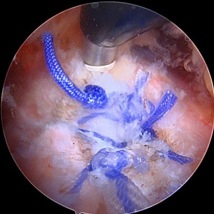

Operative Treatment for Proximal Hamstring Tears

Minimally invasive surgery can be performed either through one small incision in the posterior thigh (as seen below) or through 3-4 poke hole incisions with the use of a camera and special instruments. The tendons are reattached to the posterior pelvis (ischium) with suture anchors.